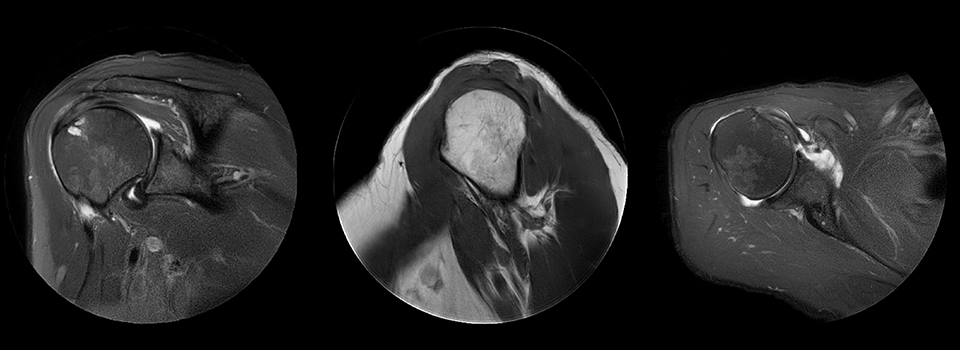

MultiVane was used for motion reduction in this shoulder examination, providing excellent detail that is not obscured by motion artifacts, as happens quite commonly when no proper motion reduction method is available. Images from Ingenia Ambition.

Cor T2W fatsat Scan time 3:06 min

Voxels 0.5 x 0.5 x 3 mm, recon 0.4 x 0.4

Sag T1W Scan time 4:10 min

Ax PD fatsat Scan time 4:17 min